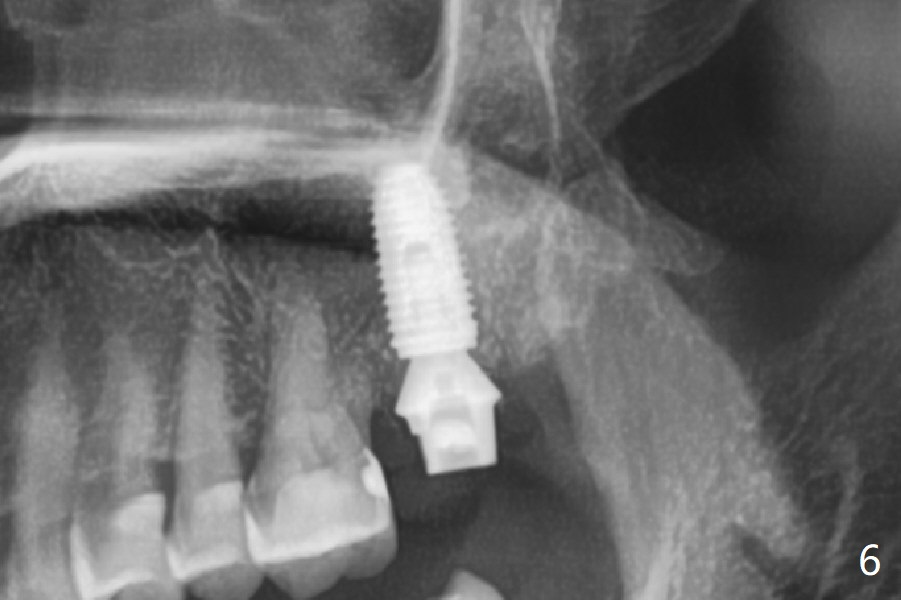

While the tooth #2 has a mesiodistal crack line with symptom (Fig.1 arrowheads, crown pending), the tooth #15 has a mesiodistal fracture (Fig.2). Immediately preop 5x5 cm CBCT (Fig.3) confirms the palatal (P) fracture with palatal bone loss. Although a 5x7.3 mm implant fits the site by design (Fig.4), a much longer implant is required to achieve primary stability past the sinus floor using IBS Magic Expanders (Fig.5,6 (20-30 Ncm; sinus lift with PRF membrane and allograft)). In contrast, primary stability could not be obtained by engaging dummy implant to the socket walls. A short implant without sinus lift is associated with less obvious complication such as fibrointegration. The implant seems osteointegrated 4.5 months postop (Fig.7). The abutment is changed to 6.5x4(5) mm before impression. There is no bone loss 5 months post cementation (Fig.8 (11 months postop)). It is the same 2.5 years post cementation (Fig.9,10).